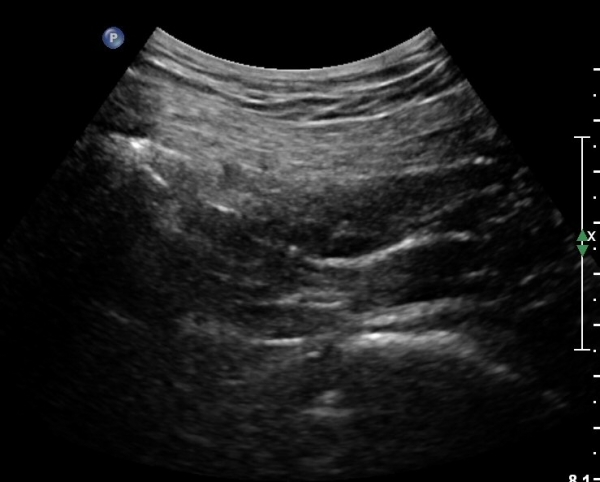

ŽÃËÀÚ¸¦ ´ëÀüÀÚ°¡ º¸À̵µ·Ï ¿ÜÃøÀ¸·Î À̵¿Çϸé Á°ñÇ¥Ãþ¿¡ ´ëÀüÀÚ·Î ÁÖÇàÇÏ´Â ÀÛÀº ³×°³ÀÇ ±ÙÀ°ÃþÀÌ °üÂûµÇ´Âµ¥ ¸Ó¸®ÂÊ¿¡¼­ ¾Æ·¡·Î SG, OI, IG, QF¸¦ °üÂûÇÒ ¼ö ÀÖ°í, ÀÌ ±ÙÀ°µé Ç¥Ãþ¿¡¼­ °í¿¡ÄÚ·Î °üÂûµÇ´Â Ÿ¿øÇü ±¸Á¶¹°ÀÌ Á°ñ½Å°æÀÌ´Ù(»çÁø 4, 5, 6, 7).